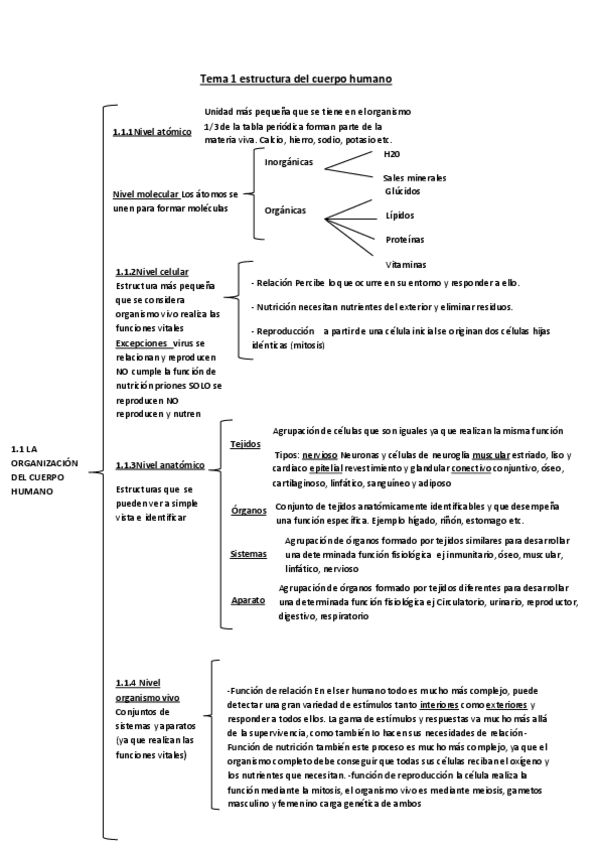

He publicado nuevos apuntes de Fisiopatología general: tema-1-estructura-del-cuerpo-humano.pdf